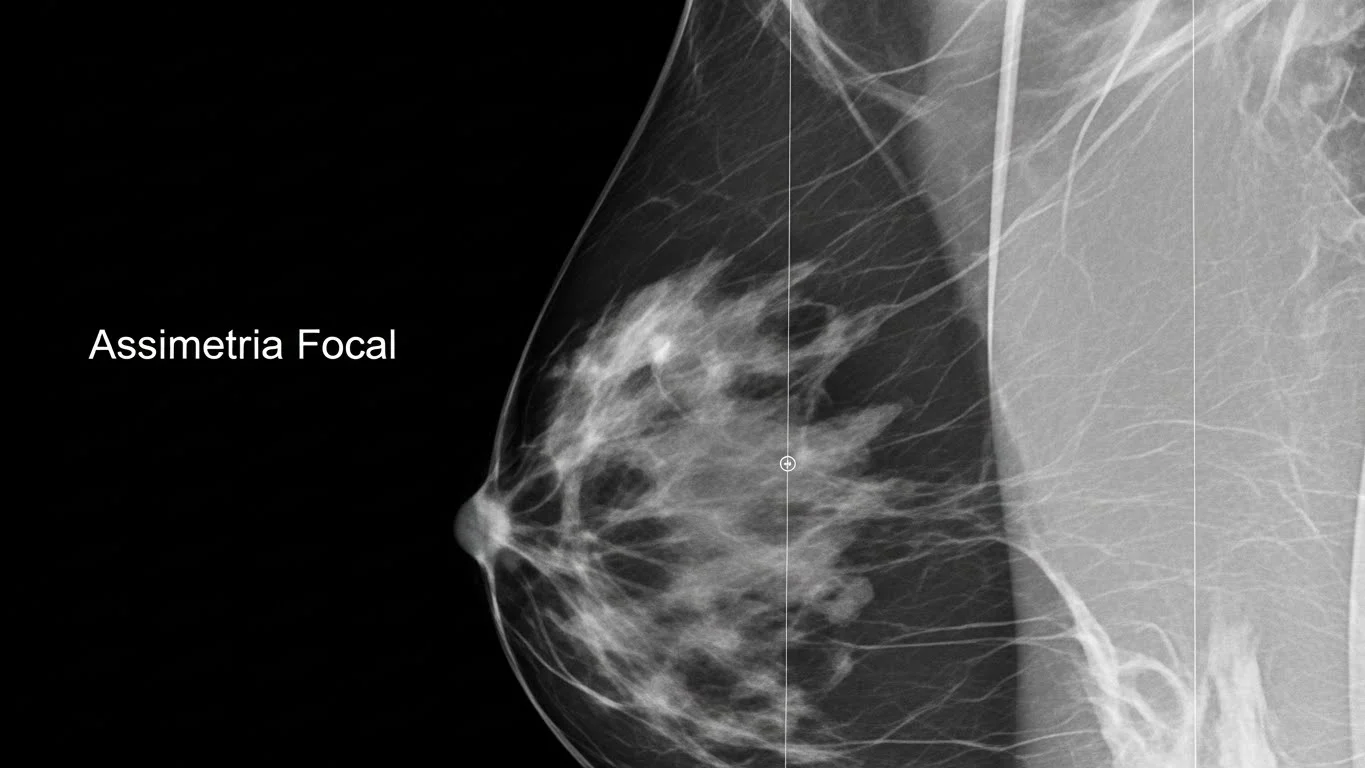

Assimetria Focal na Mamografia: o que significa e quando se preocupar? A mamografia é o principal exame de rastreamento para...